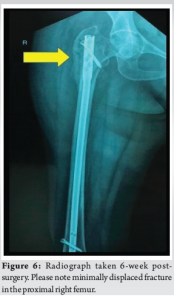

Six weeks into rehabilitation, during one of the mobilization sessions, the patient reported pain at the site of prophylactic nailing in the right femur. Radiographs revealed a minimally displaced fracture in the proximal third of the right femur (Fig. 6). Conservative management was pursued due to the absence of significant displacement or angulation, which was probably due to the prophylactic nail in situ. Mobilization was restricted to bedside exercises for 6 weeks, followed by a gradual return to full weight-bearing activity. There was no complaint of worsening of pain or any other symptoms with this conservative approach. With regular clinical and radiological follow-ups, the patient demonstrated progressive healing, transitioning to single crutch-assisted ambulation by 6 months. One-year post-surgery, complete bilateral fracture consolidation was observed (Fig. 7), and the patient achieved unaided, pain-free mobility. She is still under follow-up and is doing well, with no further symptoms so far.